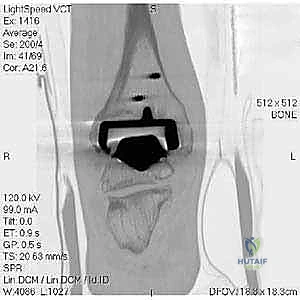

- الأشعة السينية مع تحميل الوزن (Weight-bearing X-rays): لتقييم الزوايا الميكانيكية وتحديد مدى هبوط المفصل أو وجود كسور في الكعب.

- التصوير المقطعي المحوسب (CT Scan): وهو الأداة الذهبية لتقييم "المخزون العظمي" (Bone Stock). يوضح بدقة حجم الأكياس العظمية ومقدار العظم المفقود الذي سيحتاج لترقيع.

* مراجعة المفصل (Revision Arthroplasty): إزالة المفصل القديم وتركيب مفصل جديد مخصص للمراجعة (بسيقان معدنية أطول لضمان الثبات في العظم السليم).

* دمج الكاحل (Ankle Arthrodesis): إذا كان التآكل العظمي هائلاً ولا يسمح بتركيب مفصل جديد، يتم إزالة المفصل الصناعي ودمج عظمة الساق مع عظمة الكاحل باستخدام مسامير وصفائح معدنية وطعوم عظمية.

الخطوة الخامسة: تركيب المفصل الجديد أو الدمج

يتم إدخال المفصل الجديد المخصص للمراجعة، والذي يحتوي غالباً على سيقان (Stems) تدخل عميقاً في عظمة الساق وعظمة الكاحل لضمان الثبات الميكانيكي. في حال وجود كسور في الكعب، يتم تثبيتها في هذه المرحلة.